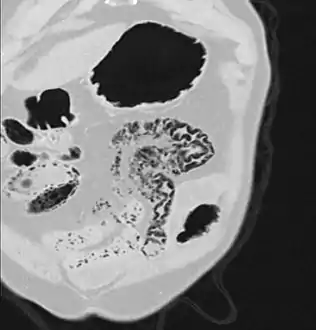

Pneumatosis intestinalis in the coronal computed tomography in lung window. It can be seen next to gas entrapment in the bowel wall and gas in the stomach wall and in numerous vessels, including the portal vein into the liver.